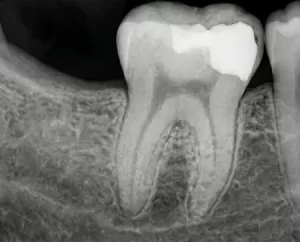

Для начала стоматолог внимательно осматривает зуб и проводит требуемые диагностические процедуры. Лечение каналов требует обязательной рентгенографии для оценки состояния тканей и степени поражения.